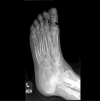

Figures